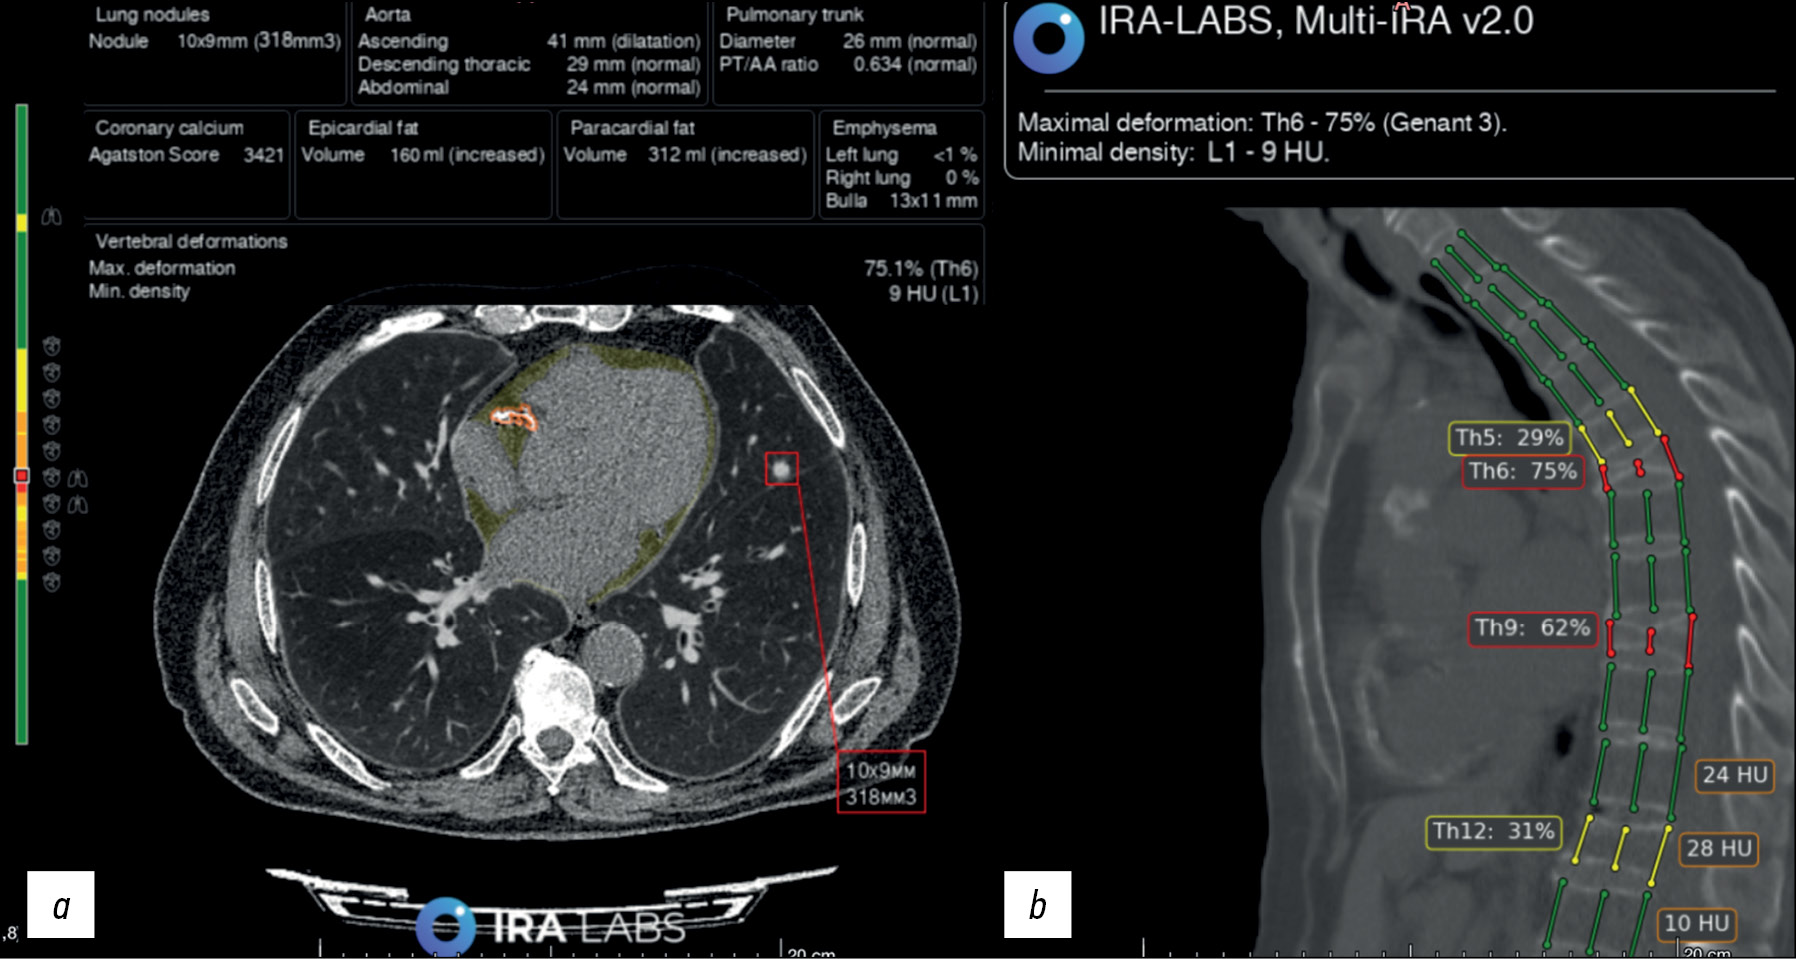

Fig. 6. An example of AI use. Patient B, 76 years old. A radiologist correctly identified bilateral hydrothorax and emphysematous changes but did not describe the lung nodule in the right lung. An AI algorithm revealed all three pathological findings: hydrothorax is highlighted with a yellow line, emphysematous changes are highlighted in orange, and the lung nodule is indicated by a red square.

Fig. 7. An example of AI use. Patient B., 79 years old. Chest CT scans: a) axial section: a radiologist and an algorithm correctly identified a lung nodule in the left lung (indicated by a red square) and coronary calcification (outlined by an orange line). In addition, the algorithm indicated an increase in the volume of epicardial fat (filled in yellow; this pathological finding was not considered in the study); b) sagittal section: a radiologist and an algorithm correctly identified compression fractures of Th6 and Th9 vertebral bodies, Genant 3 (three columns are marked with red lines); however, the radiologist did not indicate deformities of Th5 and Th12 vertebral bodies, Genant 2 (three columns are marked with yellow lines) in the protocol.